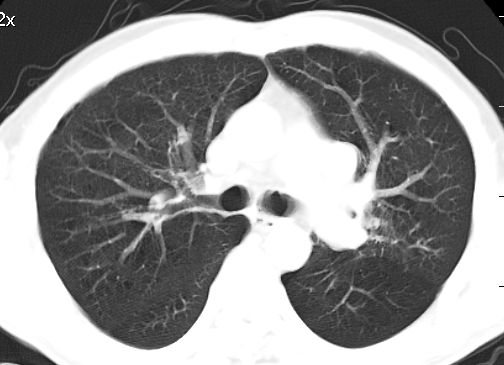

标题: CT10147:男、55岁,咯血10天,有结核病史。 [打印本页]

标题: CT10147:男、55岁,咯血10天,有结核病史。

左上肺见软组织密度肿块影,边缘呈分叶状,可见毛刺,肺门纵隔淋巴结增大,考虑左侧周围型肺癌。左上肺陈旧性结核纤并维化。

左肺分叶状肿块,有毛刺,肺门淋巴结增大.支持左周围型肺癌,肺门淋巴结转移,陈旧性肺结核.

左上肺尖后段上面陈旧性结核,下面邻近左肺门旁可见软组织肿块影,与上肺v关系密切,左肺门及气管隆突下可见增大的淋巴结影,考虑1.左上肺ca(周围型)伴肺门纵隔内淋巴转移 2.左上肺陈旧性tb